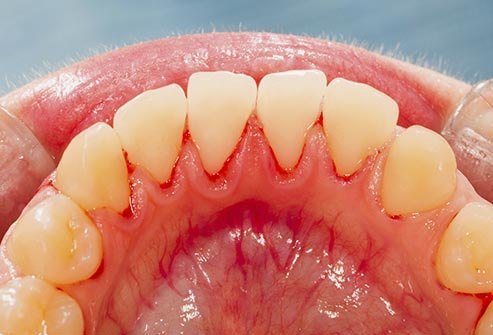

Problemet me Mishra

A rrjedh gjak lehtë nga mishi i dhëmbëve tuaj? A është gjendja për t’u brengosur? A e vëreni tërheqjen nga dhëmbët? Kjo mund të jetë faza e hershme e sëmundjes se mishit të dhëmbëve (gingivitis) ose faza më e avancuar (periodontitis). Një pllakëz e ndërtuar dhe bakteriet e ngjitura poshtë vijës së mishit e shkaktojnë atë. Mostrajtimi i periodontitis mund të shkaktojë humbjen e eshtrave dhe dhëmbët tuaj mund të ndryshojnë ose të bëhen të lëvizshëm. Kjo gjë mund ta bëjë të vështirë përtypjen, madje edhe të folurit. Për të shmangur sëmundjet e mishit të dhëmbëve pastroni dhëmbët me brushë dhe pe, shpëlarni me një gargarë dhe vizitoni dentistin tuaj regullisht për pastrim.